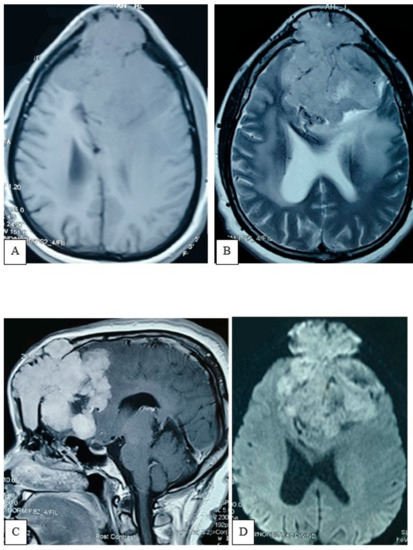

2.4.3. Preoperative Imaging

2.4.4. Surgical Procedure